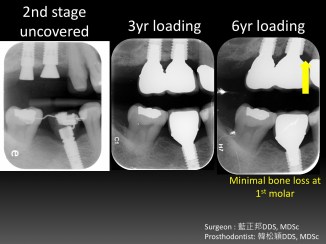

Vertical Ridge Augmentation – Case A